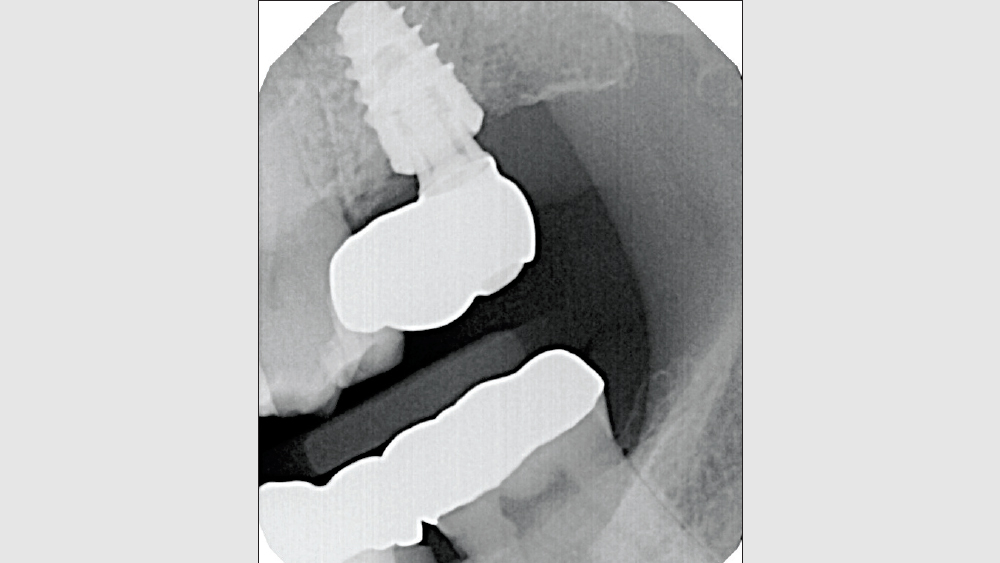

A patient presented with issues concerning a screw-retained crown in the area of tooth #15. She complained that the crown felt loose, was causing food entrapment and was difficult to clean. Upon examination, it appeared that the prosthetic screw was loose and the restoration was mobile. Removal of the crown confirmed that the current design of the prosthesis created a food trap and was not conducive to soft-tissue health. We agreed that the restoration needed to be replaced. A screwmentable restoration was the optimal solution because the malposition of the implant could be corrected by a custom abutment, thereby minimizing the cantilever. We wanted to improve the direction of loading and lessen sheer forces on the implant site by building the restoration out with the titanium structure of the custom abutment. At the same time, because the implant site was in a hard-to-reach area from which cement removal would have been difficult, screw retention was preferred.